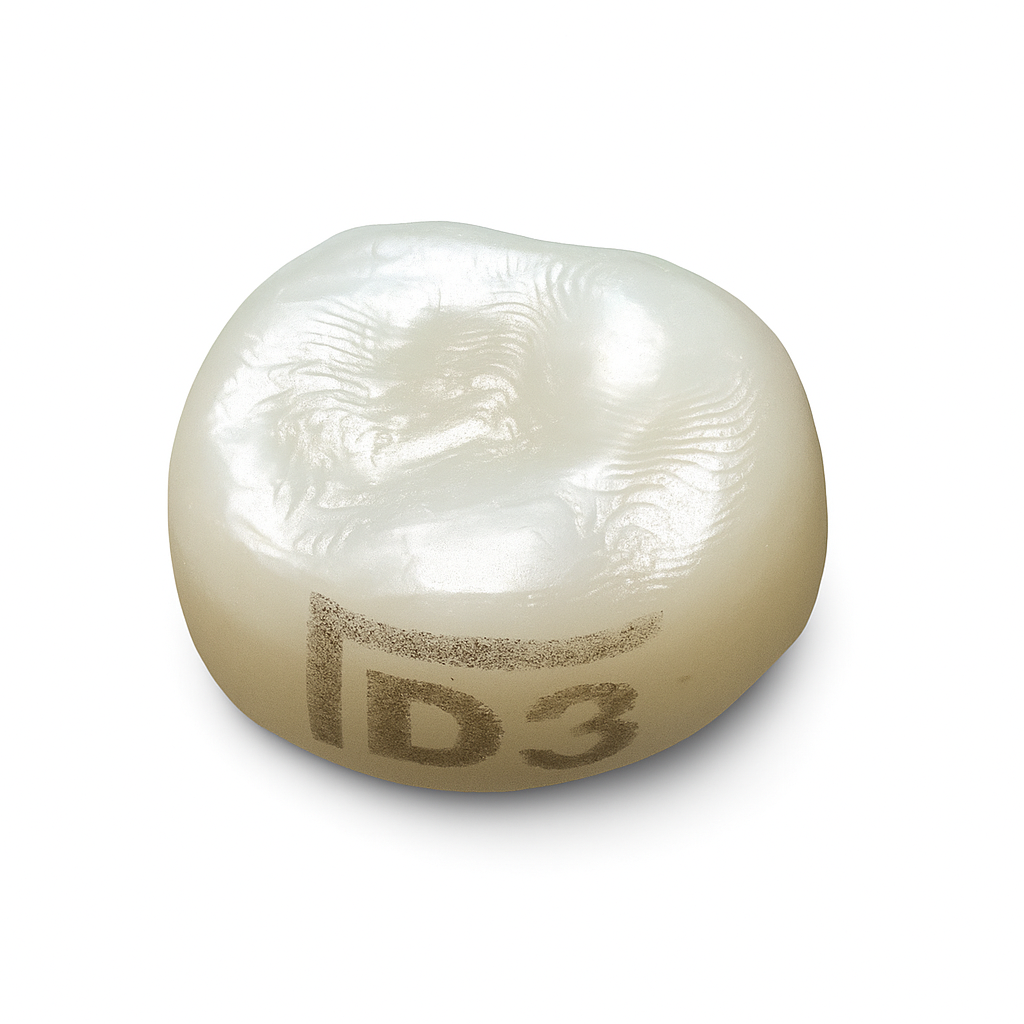

A: A pediatric dental crown, also known as a pedo crown, is a specialized dental restoration designed for children with primary (baby) or permanent molars that have suffered decay, damage, or fractures. These crowns are custom-fitted caps that cover the entire tooth, restoring its shape, strength, and function. Pediatric dental crowns are crucial in preserving the integrity of primary teeth, ensuring proper dental development, and preventing premature tooth loss in young patients. They are available in various materials, such as stainless steel, polycarbonate, and transparent strip, to suit different clinical needs and preferences.

A: On primary teeth, stainless steel crowns (SSCs) are commonly used. Stainless steel crowns are pre-fabricated crowns made of stainless steel material. They are durable, cost-effective, and can be easily adapted to fit the primary tooth's shape and size. These crowns are often used for molars and sometimes for anterior teeth when extensive restoration is needed.

A: Dentalkart offers a wide range of pediatric crowns, including stainless steel primary crowns, stainless steel primary molars, stainless steel permanent molars, polycarbonate crowns, and transparent strip crowns.

A: The choice of pediatric crown depends on various factors such as the tooth's position, size, and condition. Stainless steel crowns are ideal for posterior teeth, while polycarbonate crowns are suitable for anterior teeth. Transparent strip crowns are useful for esthetic concerns.